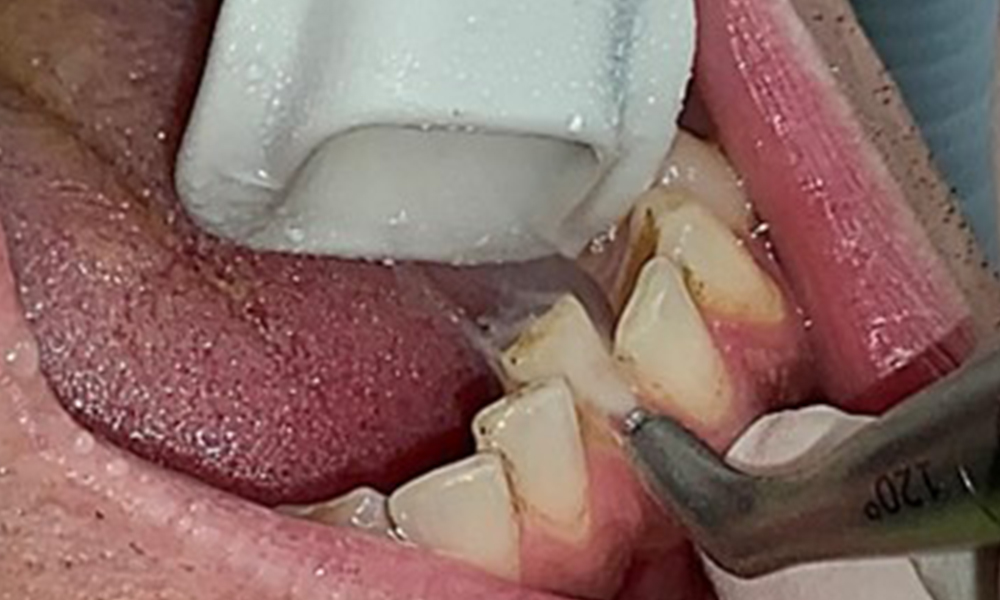

Ziel ist es durch supra- und subgingivale Biofilmentfernung das Erkrankungsrisiko zu kontrollieren. Die Wahl der Instrumente erfolgt

bedarfsgerecht. Zunächst sind Zahnstein und ggf. Konkremente mit Ultraschall und / oder Handinstrumenten zu entfernen (Abb. 10).